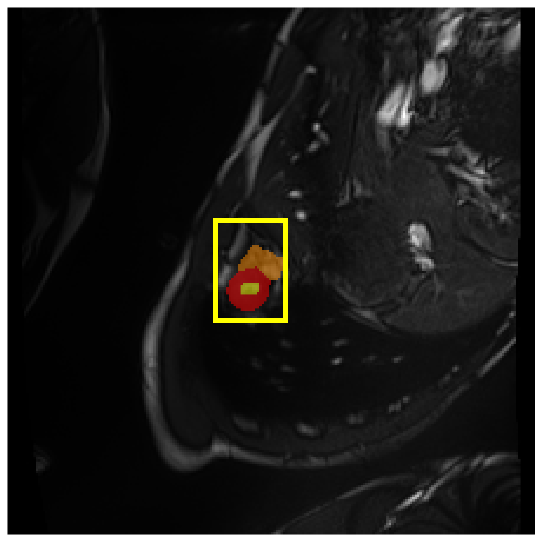

4.3.2 Visual Comparisons

Visualization of our method on the Synapse and ACDC datasets is shown in Fig. 3(a) and Fig. 3(b). For the Synapse dataset illustrated in Fig. 3(a), FCT failed to accurately segment SM and GB, while MERIT achieved precise segmentation of SM but struggled with GB. In contrast, our method achieved accurate segmentation of both SM and GB. Regarding the ACDC dataset shown in Fig. 3(b), while previous methods achieve comparable segmentation of the Myo and LV to the GT, they exhibit noticeable errors on the RV, including invasion into adjacent organs and misrecognition. On the other hand, our method accurately segments across all three structures Myo, LV, and RV, performing as precisely as the GT. We demonstrate the superiority of our method quantitatively and qualitatively.